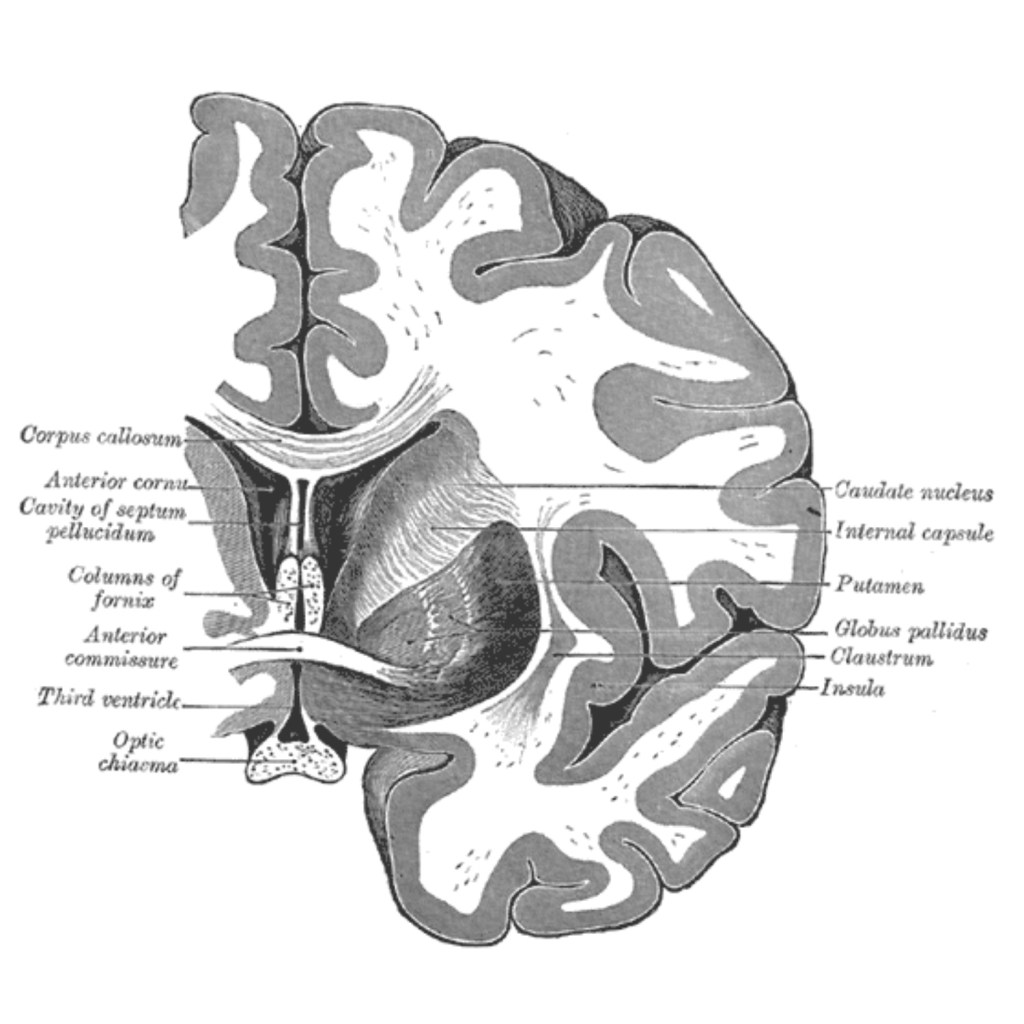

Ich habe letztens die erste Folge von Das Hausboot geschaut und irgendwie kam mir da schon der Gedanke, dass ich mal was zu Eisen- und Kalkablagerungen im Gehirn schreiben könnte. Weiß nicht, ob das jetzt mehr wegen Gunter Gabriel oder dem Hausboot an und für sich war. Und dann hatten wir prompt einen Patienten mit…

-